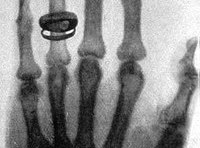

Одесса была в числе первых центров нового направления медицины – рентгенологии. 8 марта 1925 года основано Одесское научное общество рентгенологов.Так, доктор Яков Моисеевич Розенблат прошел курс специализации по вопросам медицинской химии в лабораториях Берлина и в Институте Пастера (Париж). По возвращении он основал в Одессе один из первых в России Частный химико-бактериологический институт.

Яков Розенблат стал одним из ведущих специалистов Европы по рентгенологии. Он же стоял у истоков организации кафедры рентгенологии в рамках Одесского клинического института, а впоследствии и в Медине. Назначенный заведующим кафедры, утвержденный в звании профессора Я.М.Розенблат читает студентам Медицинского института цикл лекций по основам рентгенологической специальности.